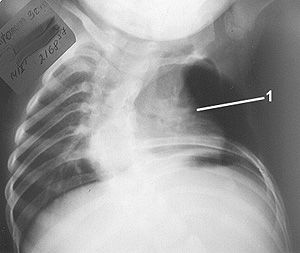

Рис. 5. Рентгенограмма и схема грудной клетки до операции б-ной Г. 2 лет с левосторонним синдромом Поланда и врожденным сколиозом.

Рис. 6. Рентгенограмма и схема грудной клетки до операции б-ной Г. 2 лет с левосторонним синдромом Поланда и врожденным сколиозом.